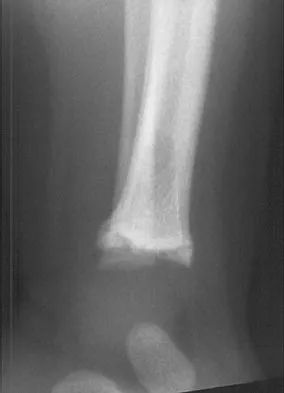

Question 49 High Yield

A 14-year-old girl reports a 3-week history of anterior thigh pain and a palpable mass after sustaining a soccer-related injury. Examination reveals a tender, firm mass in the midportion of the rectus femoris. MRI scans are shown in Figures 39a through 39c. What is the most appropriate management?

Detailed Explanation